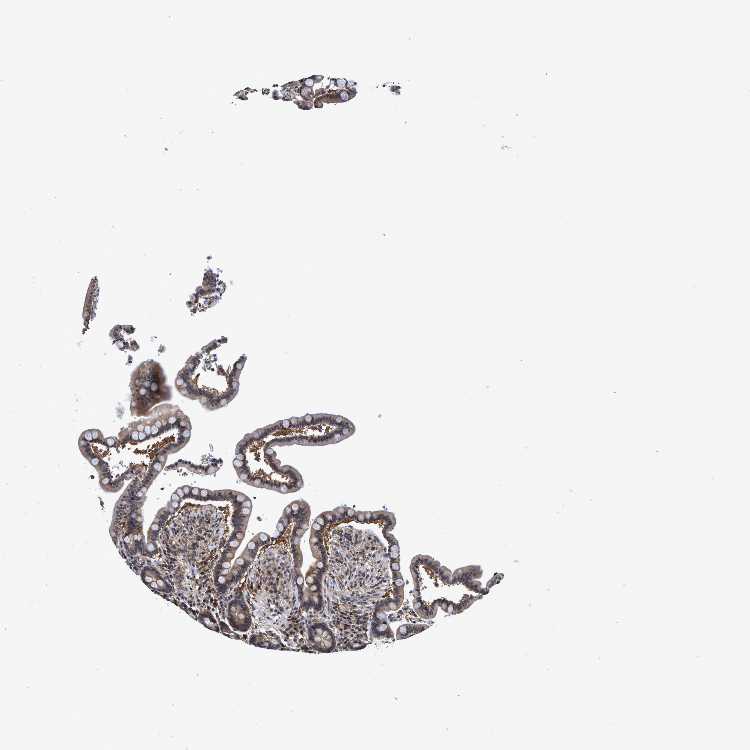

COLON - Antibody stainingi

Antibody staining in the annotated cell types in the current human tissue is reported as not detected, low, medium, or high, based on conventional immunohistochemistry profiling in selected tissues. This score is based on the combination of the staining intensity and fraction of stained cells.

Each image is clickable and will lead to virtual microscopy that enables deeper exploration of all samples and also displays staining intensity scores, fraction scores and subcellular localization as well as patient and tissue information for each sample.

Antibody HPA023119

Endothelial cells Low

Glandular cells Medium

Peripheral nerve/ganglion Medium